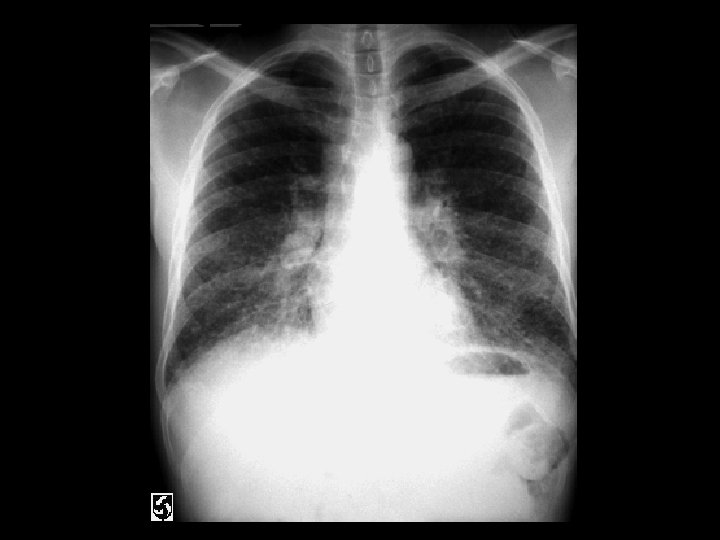

Left hydropneumothorax • Findings: – left pnuemothorax – left pleural effusion (possibly blood) • causes: – penetrating trauma – iatrogenic – bronchopleural fistula